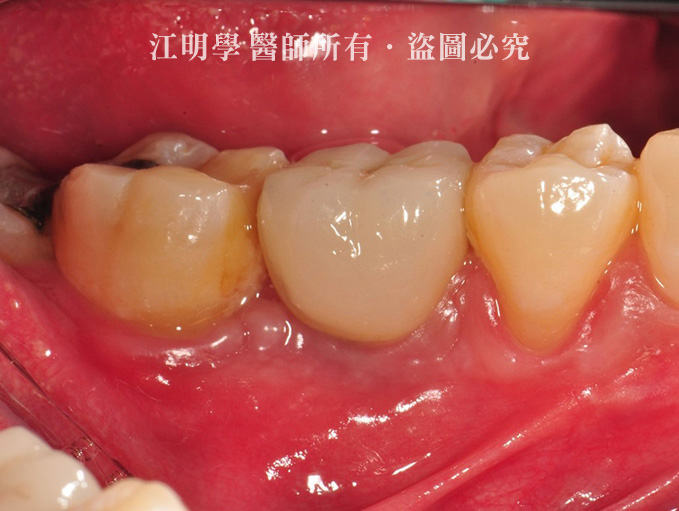

治療後

治療後:提供上排臼齒支撐力,避免牙齒繼續位移以及牙床萎縮。